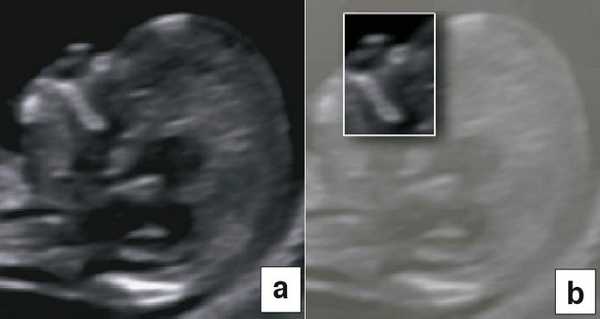

Воротниковое пространство

В начале 90-х годов прошлого века в практику был внедрен метод измерения толщины воротникового пространства (ТВП) в I триместре беременности, и к настоящему времени его считают показателем не только анеуплоидии, но и широкого спектра наследственных синдромов и пороков развития [2]. K. Николаидес (K. Nicolaides) с группой исследователей предложили новую модель скрининга на анеуплоидию и установили правила использования этого метода, в частности необходимость применения кривой обучения, проведения аудита, качественного (процедура оценки качества изображений) и количественного (медиана, дельты-ТВП и т.д.). Фонд медицины плода (Fetal Medicine Foundation) стандартизировал предложенный ими клинический протокол и установил правила сертификации для повышения качества медицинской помощи и уменьшения изменчивости результатов данных скрининга [3, 4]. Измерение ТВП можно проводить вручную (рис. 2a) или полуавтоматически (рис. 2b), чтобы результаты измерений были более воспроизводимыми. Кроме того, компания Samsung разработала дополнительный метод измерения показателей ТВП - 5D NT, позволяющий точно выявить срединно-сагиттальную плоскость и улучшить оценки по шкале Германа (Herman score).